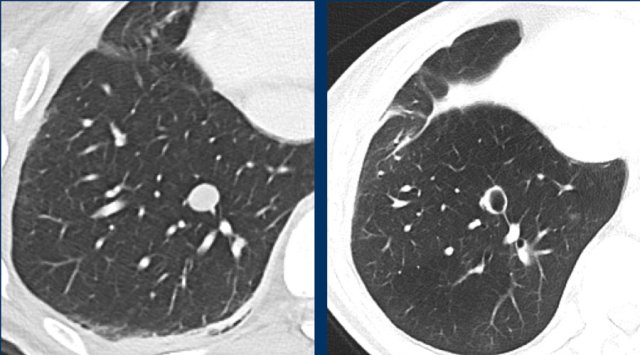

Cavitating lesions

Cavitation can occur during treatment.

Cavitating lesions should be continuously measured in their longest diameter.

A different assessment can be provided if the sum of the longest diameters does not adequately correspond to the patients response assessment.

These CT images are of a 32-year-old male with a pulmonary metastasis of a malignant peripheral nerve sheath tumour.

Cavitation occured after treatment with pazopanib, but the size remained the same.

Although the size remains the same, a remark can be made in the report, that the actual tumorvolume has decreased.